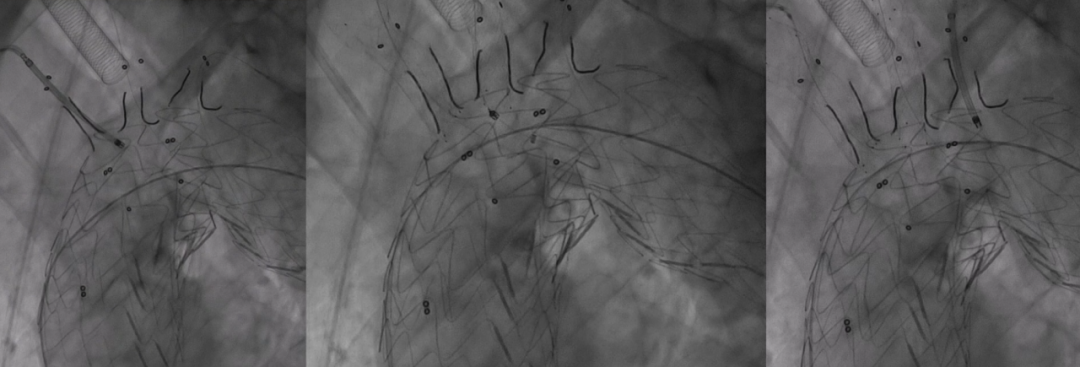

5. 支架释放与球囊预扩

释放支架主体,之后,头端后释放打开后将支架输送系统缓慢撤出。

分别经分支导丝送入球囊扩张支架分支覆膜部分,确保贴附良好。

6. 裸支架置入,球囊后扩张

于无名动脉、左颈总动脉及左锁骨下动脉开口位置处释放裸支架,维持血流通畅。

球囊后扩,优化支架形态及贴壁性,减少内漏风险。